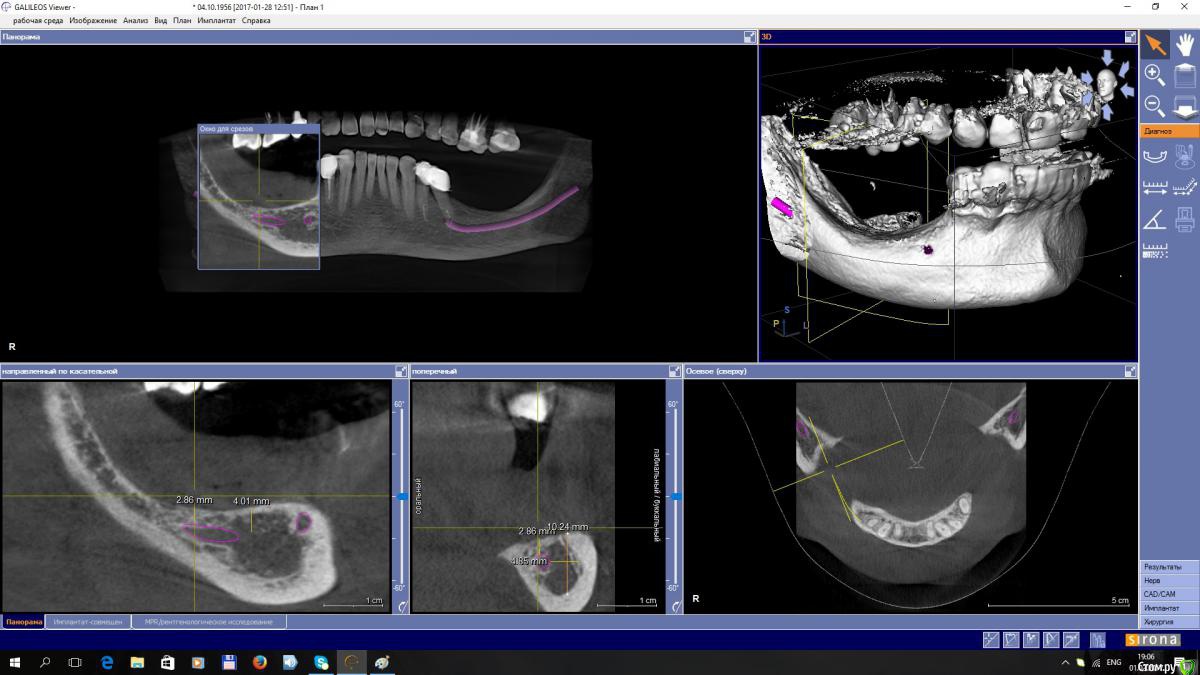

EEcho Опубликовано 3 февраля, 2017 Поделиться Опубликовано 3 февраля, 2017 Уважаемые коллеги! Я в раздумье.Максимально, кость я могу поднять на 4-5 мм, с одной и с другой стороны. Дальше не позволяет межальвеолярная высота.Делать репозицию нерва или все таки пластику с последующей постановкой коротких имплантов. Ссылка на комментарий